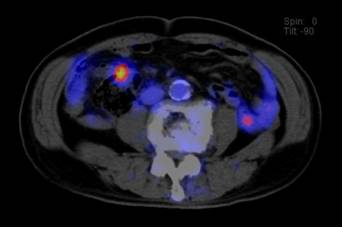

大腸がんの患者さんの実際の写真を示します。図1のPET画像では、腫瘍の活動性がよくわかります。図2のCT画像では、腫瘍の形がわかりますが、これだけでは診断は難しい像です。図3のPET-CT画像では、腫瘍の形と活動性が両方ともわかり、自信を持って大腸がんと診断できます。

肺がんの患者さんの実際の写真を示します。図4、図5のPET-CT画像で、肺がんが小さいリンパ節に転移している様子が明瞭に示され、治療方針を立てるのに役立ちます。

![]() |

| 図 4 PET - CT 画像 | 図 5 PET - CT 画像 |